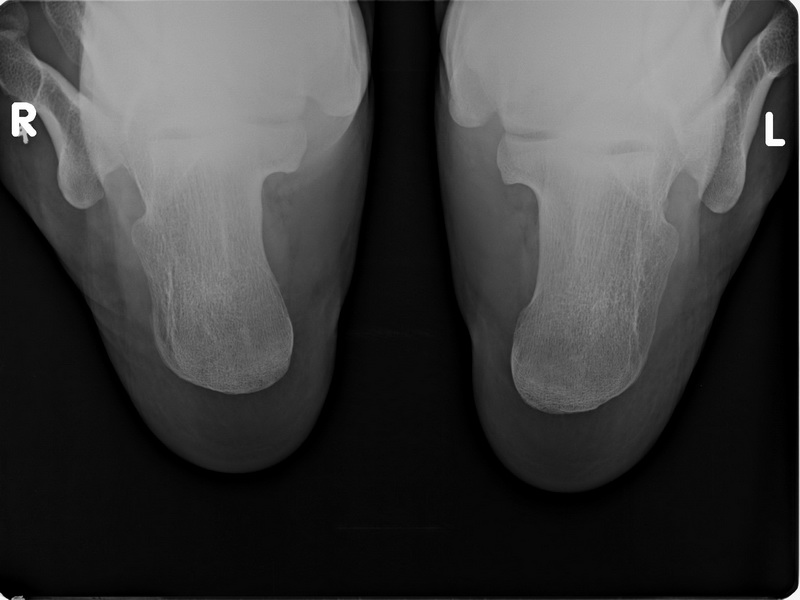

标题: X6080:双跟骨轴侧位,有双侧跟骨骨刺形成吗?好像是跟骨结 [打印本页]

标题: X6080:双跟骨轴侧位,有双侧跟骨骨刺形成吗?好像是跟骨结

双跟骨轴侧位,有双侧跟骨骨刺形成吗?好像是跟骨结节呀?

双侧跟骨下结节处未见明确骨刺形成。

双侧跟骨下结节处未见明确骨刺形成--------------

未见明显骨刺形成,但是侧位不侧,像斜位

比较毛糙,还是有骨质增生

我认为在私营医院,最多弄个轻度骨质增生诊断,要说双侧跟骨骨刺形成,就太过度了。如是在公立医院我就当正常好了,等以后真得有骨刺了再报也不迟。

双跟骨下结节未见明显骨刺形成。